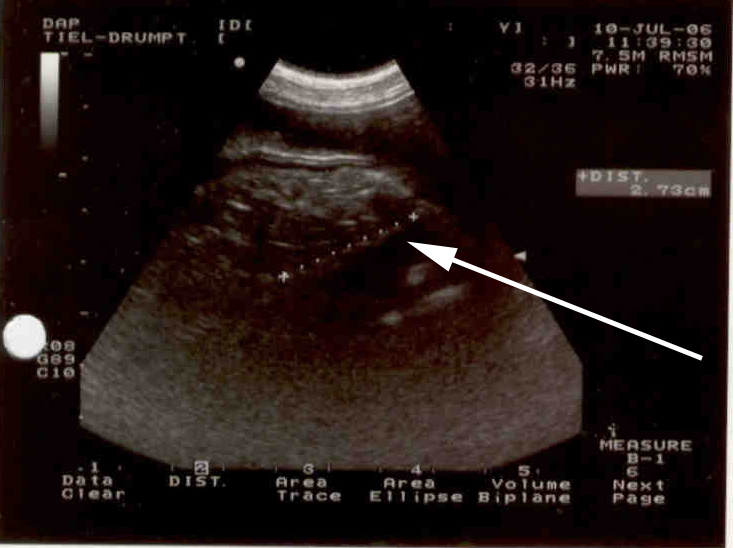

Met de echo zagen we ook een verdachte structuur: